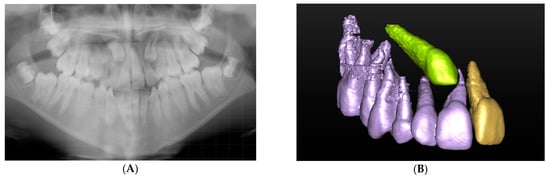

The CBCT scan reports proved invaluable in assisting the clinicians confirm and guide the surgical treatment plan and thus justified the radiation dose, as demonstrated in Figure 2. The panoramic and upper standard occlusal radiography aided in the detection of a mixed complex-compound odontome in the left anterior maxilla, but provided insufficient information for management and treatment planning. The capacity of CBCT to provide three-dimensional multiplanar reconstruction of the region of interest allows visualisation of the anatomical structures possible from all viewpoints. This aided in the surgical excision of the odontome to minimise any damage to adjacent teeth and structures.

Figure 2.

(A) Panoramic radiograph showing a mixed complex-compound odontome in the left anterior maxilla. (B) Upper standard occlusal view of the mixed complex-compound odontome. (C) CBCT axial view demonstrating the full extent of the odontome and its relationship to the teeth.